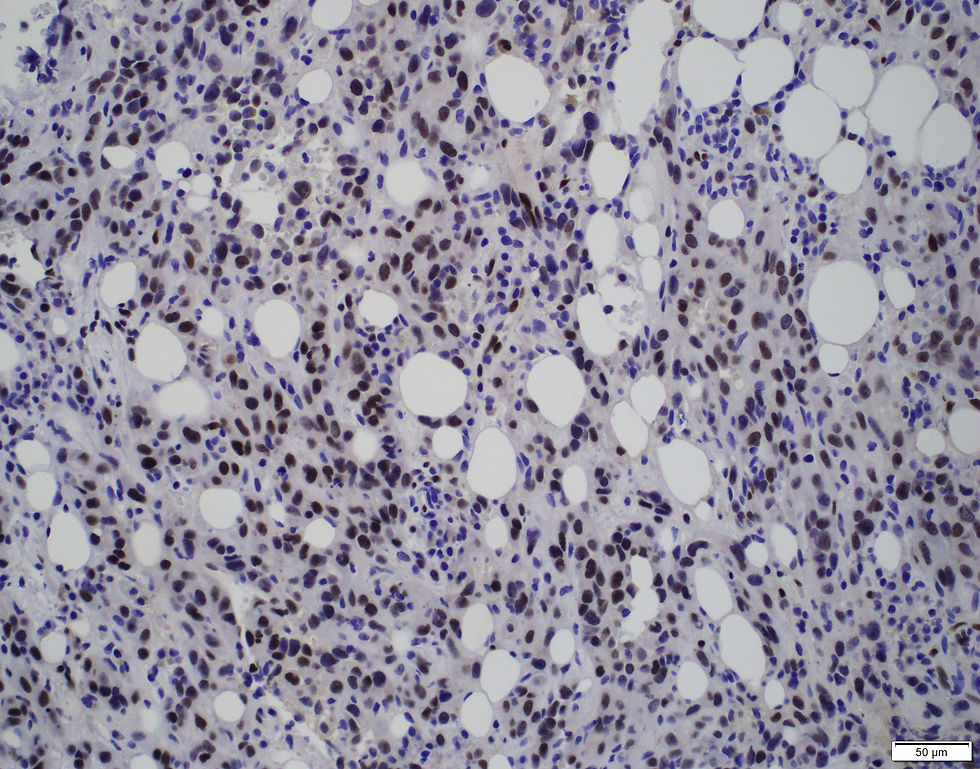

The correct answer is D. The immunostains are ERG and CD31. This is a case of epithelioid hemangioendothelioma in the bone.

Immunohistochemically, EHE expresses endothelial markers including CD34, CD31, podoplanin (D2-40), FLI1, and ERG, though staining intensity may vary. Approximately 40% of cases express epithelial markers like CK7, CK8, CK18, and pan-keratin, while EMA expression is rare. SMA is positive in about half of the cases.